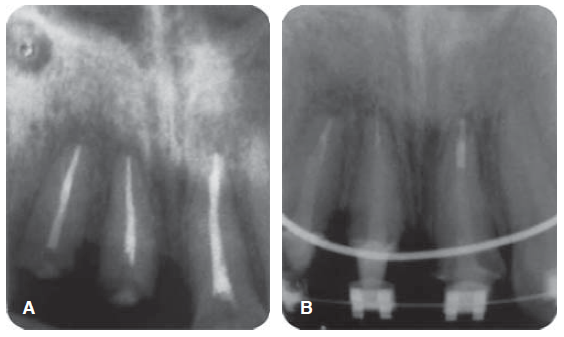

En la exploración clínica extra e intraoral sólo se observa la fractura dental (Figura 26), en la radiografía se observa el tratamiento de sistema de conductos (Figura 27).

Fractura complicada de corona del diente 21, radiográficamente se observa un diente despulpado con tratamiento de sistema de conductos y sin lesión periapical; periodontalmente presenta gingivitis inducida por placa dentobacteriana (Figura 28).

Reconstrucción con poste de fibra de vidrio

Desobturación con instrumentos de compactación vertical de Schilder, tratando de sellar mejor al momento de termoplastificar la gutapercha, se toma radiografía control de desobturación, observando que el Drill del sistema a utilizar queda con espacios (Figura 29 A), se ajuste del poste de fibra de vidrio FRC Postec ® Plus tamaño 3, de la casa comercial Ivoclar Vivadent, cuyo diámetro coronal es de 2 mm y el apical de 1 mm (Figura 29 B). Se corta el poste de fibra de vidrio en una intensión con pieza de alta velocidad, fresa de diamante grano grueso y abundante irrigación, luego se graba, se lava, se seca el conducto y se cementa el endoposte de fibra de vidrio con la parte coronal del mismo hacia apical del conducto para de esta forma ser más congruentes con el diámetro de un diente joven y el excedente apical del poste se introduce como poste complementario en coronal del conducto, la cementación y reconstrucción coronal se realizó con el sistema del cemento resinoso Rebilda DC ® (VOCO), finalmente se toma una radiografía control de cementación (Figura 29 C).

Figura 29 A) Desobturación. B) Prueba del poste de fibra de vidrio. C) Cementación del poste de fibra de vidrio.